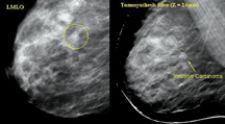

Breast imaging is no longer a single modality specialty. Although mammography continues to lead the pack as the most accurate, accessible and cost-effective screening modality, MRI and ultrasound are quickly becoming elevated to the same standard of care, particularly for women at high risk.

evidence that demonstrate the clinical utility of breast MRI for finding cancer that other tests could not detect. A study in the March 29, 2007 issue of the New England Journal of Medicine, released to coincide with the publication of the new guidelines, looked at 969 newly diagnosed breast cancer patients to determine if MRI could detect contralateral cancers that physical exams and mammograms missed. In thirty women, MRI detected clinically and mammographically occult breast cancer in the other breast; 18 were confirmed positive for invasive cancer after biopsy.(2)

More recently, a prospective pilot study of screening mammography, MRI and ultrasound in asymptomatic women 25 years of age or older and genetically at high risk found that MRI helped detect more cancers than the other two modalities. However, MRI also led to a higher rate of biopsies..(3)

ECRI, an independent nonprofit health services research agency, also released a report that found the use of both MRI and X-ray mammography for screening detect more cancers than mammography alone. Lead author Wendy Bruening, a senior analyst at ECRI, also found a higher rate of false positives with MRI. She noted, “But for women at high risk of cancer, the benefit of finding more cancers earlier may outweigh the harms of unnecessary testing.”

However, another recent study found the use of CAD with MRI may improve standardization and the analysis of benign and malignant lesions, potentially reducing the number of false positives and unnecessary biopsies. The retrospective study looked at 154 suspicious breast lesions visible and biopsied by MRI guidance. Recommendations made by radiologists at the time were compared to findings using CADstream breast MRI CAD software from Confirma. Analysis of the tissue enhancement data from the CAD-processed images correctly identified 38 of 41 malignant lesions and researchers reported a reduction in the false positive rate. The researchers determined that using CAD for breast MRI “significantly improved the discrimination of benign from malignant lesions when compared with that at initial interpretations by radiologists.” (4)